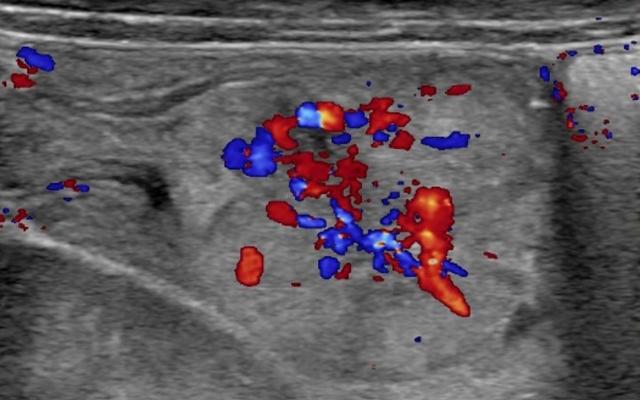

Bij lichamelijk onderzoek zagen wij een bleek, vermoeid meisje met een soepele buik. Laboratoriumonderzoek liet een ferriprieve anemie zien; de Hb-concentratie was 4,4 mmol/l. Bij aanvullend echografisch onderzoek werd een ileo-ileale invaginatie van de dunne darm gezien met zeer waarschijnlijk een poliep als anatomisch aanwijsbare oorzaak (‘leading point’) (figuur a en…